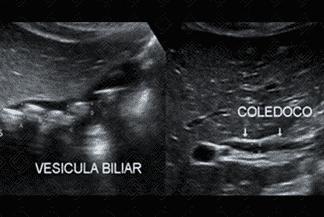

Texto alternativo para a imagem Figuras 1 e 2. Créditos: Dra. Elazir Mota - Rio de Janeiro/RJ

Descrição das figuras 1 e 2: Ultrassonografia de abdome. Imagens ecogênicas, com sombra acústica posterior, móveis durante a mudança de decúbito, sem fluxo ao Doppler colorido, compatíveis com cálculos no interior da vesícula biliar. Observa-se que o colédoco e a região infundibular foram criteriosamente analisados.

• Ultrassonografia de abdome : Exame de escolha para avaliação de cálculo biliar. Os cálculos são visualizados como imagens ecogênicas, móveis ao decúbito, com forte sombra acústica posterior;